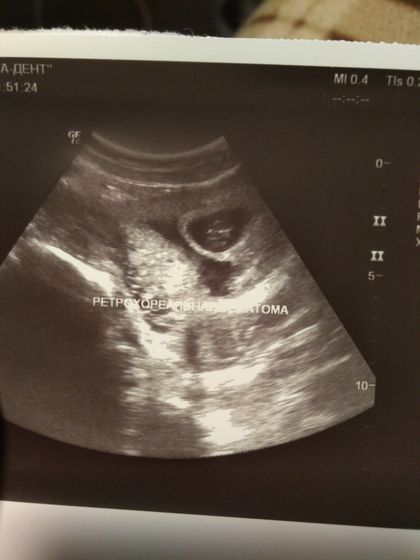

Привет девули! Была на УЗИ сегодня! И врач мне говорит, а ты не кровишь?!?!?! Я такая неееееее! Чувствую себя Оки, в плане живота ?говорит странно! Сказал показать своему врачу и на сохранение ?у кого была гематома? Она что обязательно кровить должна? Сама не пройдет?

на 1 скрин.сказали гематома, большая типо, а у меня ниче не кровит… неделю лежала на сохранении, переделывает узи др.врач, а там нет ниче! и не было, говорит там просто большой сосуд.